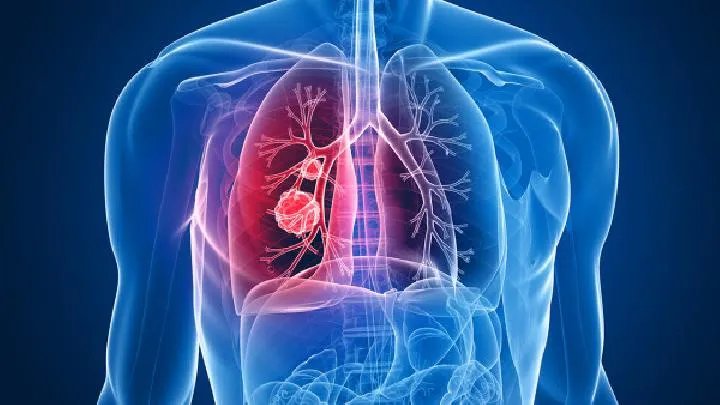

肺气肿是一种危害严重的疾病,所以一定要积极地进行治疗,而选择一家靠谱的医院时治愈疾病的关键。很多患者关心医院选择的问题,那么如何选择一家好的医院治疗肺气肿呢?我们就给大家介绍以下几种方法: